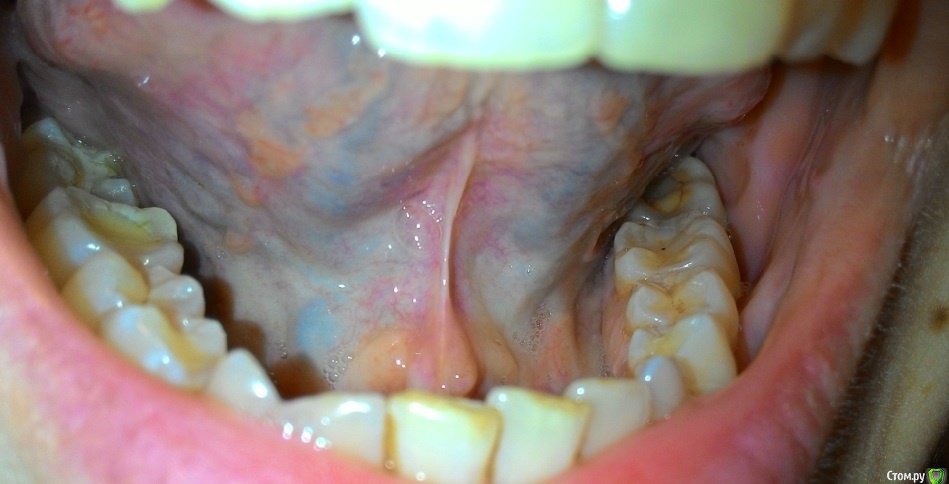

Пузырьки на уздечке под языком

На уздечке под языком у меня образовалось 2 пузырька.

28 декабря почувствовала, что как будто под языком что-то есть и оно мешается. Увидела эти пузырьки. Не болят.

29 декабря поехала снимать швы. Снимал другая доктор (мой был уже в отпуске), показала ей эти пузырьки, она сказала, что на вид пока не страшно, но что это - ей не понятно. Она показала меня еще другому доктору, та тоже сказала, что ничего страшного не видит, но толком не понимает, что это, порекомендовала наблюдать.

03 января - пузырьки сохраняются.